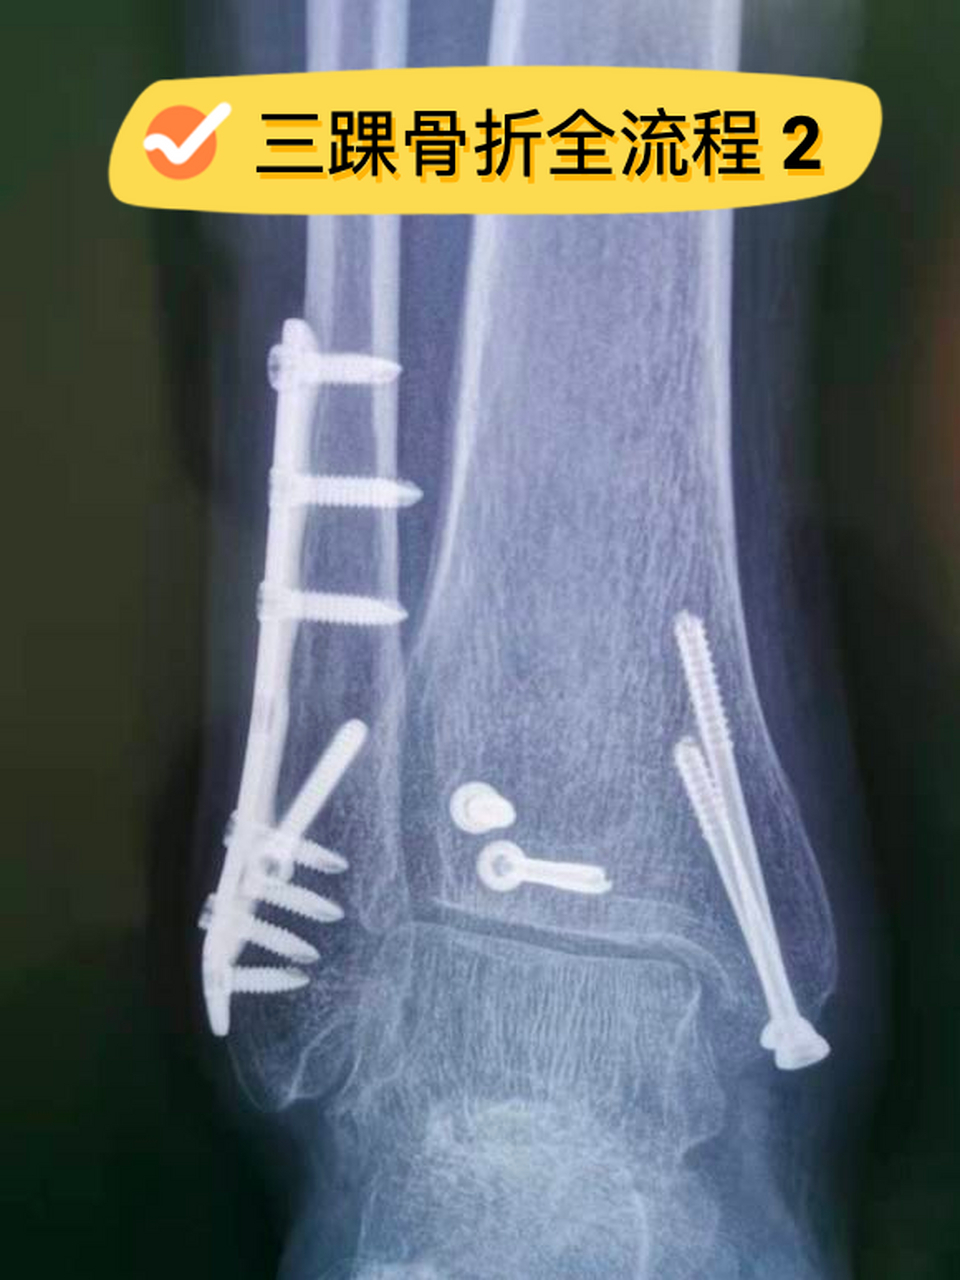

骨折(per4度),消肿抗凝治疗1周后腰硬联合下行外踝切开复位钢板内固定

后踝1/3圆型钢板固定,钢板薄,好塑形,更伏贴

三踝关节骨折脱位钢板固定